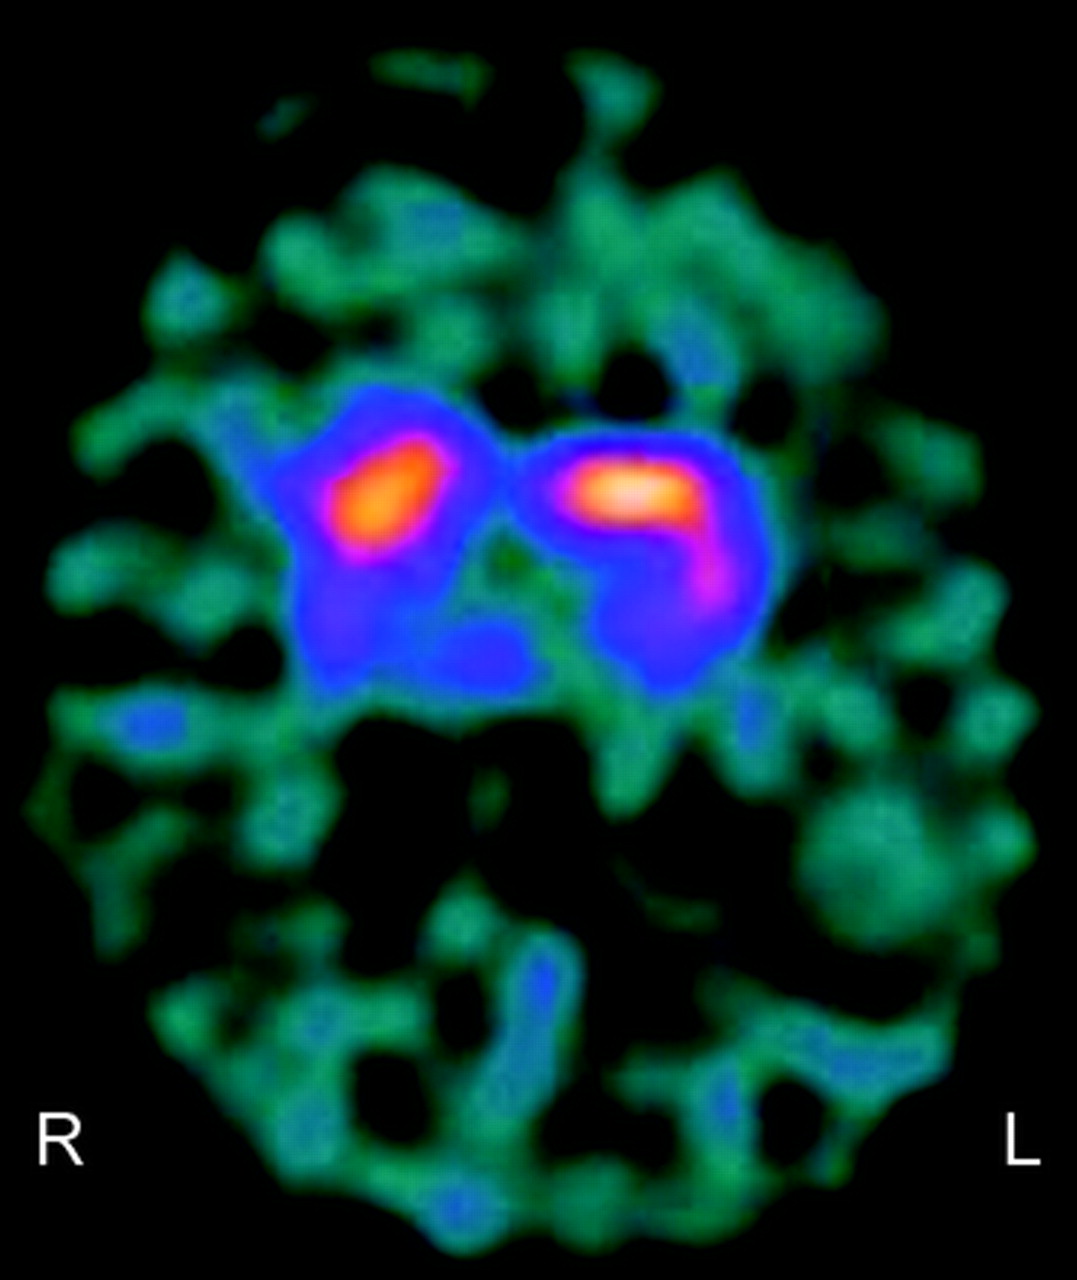

这个病人的症状是一致的不宁腿综合症(RLS)和周期性肢体运动的睡眠。药物包括泛醌。最初的血液测试包括全血细胞计数、铁、铁蛋白、葡萄糖、肾和肝脏档案、甲状腺功能测试,和维生素B12水平是正常的。是正常的神经传导研究不包括周围神经病变。由于风险发展中多巴胺缺乏综合症POLG突变,123 -我Ioflupane DatSCAN成像。

这显示不对称的示踪剂摄取相对减少硬膜吸收正确的硬膜相比,左侧(图2)符合暗示震颤麻痹的多巴胺转运体的损伤机制。她拒绝药物干预来控制症状。的结果POLG1受影响亲属的基因分析显示相同的杂合突变。